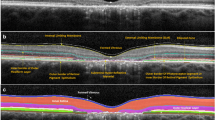

On CAMS and FMS, eight borders were defined (Fig. 1): (1) the inner limiting membrane (ILM); (2) the outer boundary of the macular RNFL (mRNFL); (3) the outer boundary of the inner plexiform layer (IPL); (4) the outer boundary of the inner nuclear layer (INL); (5) the outer boundary of the outer plexiform layer (OPL); (6) the external limiting membrane (ELM); (7) the junction between the inner and outer photoreceptor segments (IS/OS); and (8) Bruch’s membrane (BM). Using these borders, the thicknesses of the following individual and composite layers were defined: 1–2 mRNFL; 2–3 GCL + IPL (GCIP); 3–4 INL; 3–5 INL + OPL; 5–6 outer nuclear layer (ONL); 6–7 inner photoreceptor segments (IS); 5–8 ONL + photoreceptor segments (ONL + PR); and 7–8 retinal pigment epithelium (RPE+).

Example of OCT segmentation techniques. a and b: Spectralis CAMS (a) and Cirrus CAMS (b) borders: (1) inner limiting membrane; (2) outer boundary of retinal nerve fiber layer; (3) outer boundary of inner plexiform layer; (4) outer boundary of inner nuclear layer; (5) outer boundary of outer plexiform layer; (6) external limiting membrane; (7) inner/outer photoreceptor segment junction; (8) Bruch’s membrane. Layers 1–2 mRNFL; 2–3 GCIP; 3–4 INL; 3–5 INL + OPL; 5–6 ONL; 6–7 IS; 5–8 PR; 7–8 RPE+. c Spectralis FMS borders example: (RNFL) outer boundary of retinal nerve fiber layer and (IPL) outer boundary of inner plexiform layer